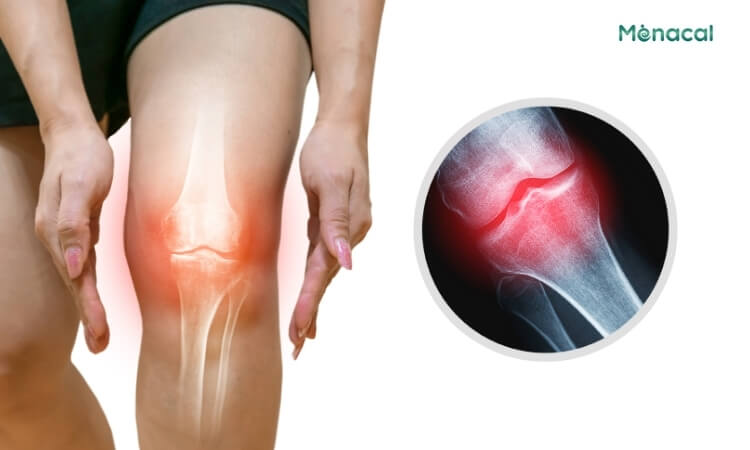

Thoái hóa khớp gối – “Thủ phạm” hàng đầu ở người trưởng thành

Đây là nguyên nhân phổ biến nhất gây ra chân vòng kiềng khi về già hoặc ở tuổi trung niên. Cơ chế cụ thể do áp lực và quá trình lão hóa, lớp sụn ở mặt trong của khớp gối bị mài mòn nhanh hơn mặt ngoài. Khi lớp sụn này mỏng đi, khe khớp bên trong hẹp lại, làm cho trục của chân bị xô lệch, khiến hai đầu gối có xu hướng bị đẩy ra xa nhau và tạo thành hình vòng kiềng.